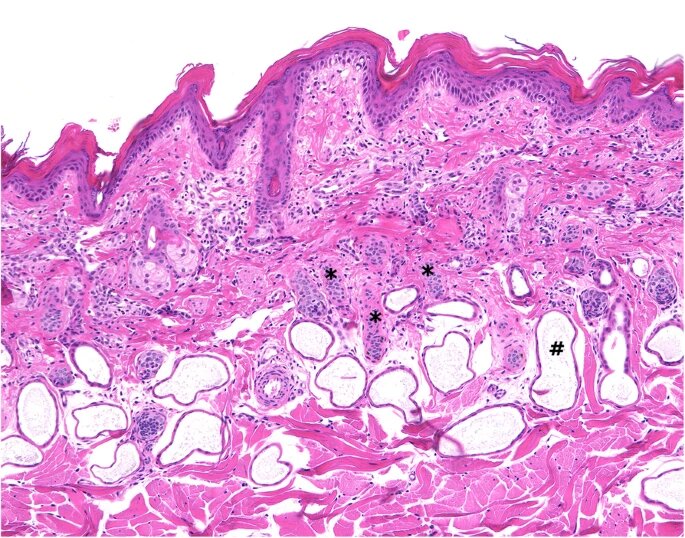

В образцах поражённой кожи наблюдался пластинчатый ортокератотический гиперкератоз эпидермиса с кератиновыми чешуйками и небольшим количеством поверхностных корок. В дерме волосяные фолликулы были мелкими, а в просветах фолликулов содержалось лишь несколько стержней волос. Кроме того, была зафиксирована минимальная периваскулярная поверхностная лимфоцитарная инфильтрация/воспаление. Не было обнаружено признаков бактериальной или грибковой инфекции, паразитарной инвазии или аутоиммунного заболевания (рис. 2).

Рис. 2.

Гистология кожи телёнка 1 в день обращения: поверхностный ламинарный ортокератотический гиперкератоз, соответствующий клинической картине (чешуйки). Волосяные фолликулы диффузно уменьшены в размере (звёздочки). Примечание: нормальное расширение апокринных желёз (#) в коже крупного рогатого скота